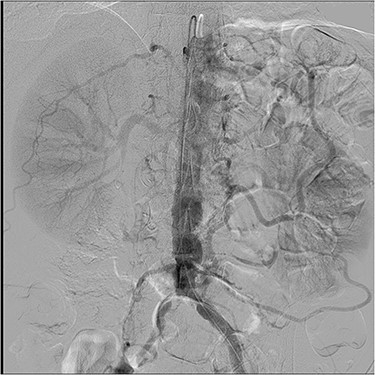

(A) Supra-celiac aorto-celiac and aorto-superior mesenteric bypass using a bifurcated Dacron graft. (B) CABG ×5 with proximal SVG anastomoses to the ascending aorta for D1, OM1, OM2 and PDA grafts. LIMA to mid-LAD graft not seen in this image.

The patient underwent uncomplicated left carotid endarterectomy and was admitted postoperatively. He had no neurologic complications and was taken for combined CABG and mesenteric bypass on the fourth postoperative day. After induction of anesthesia and placement of hemodynamic monitoring lines, the procedure was initiated with a median sternotomy and mobilization of the left internal mammary artery as a pedicled graft. The greater saphenous vein was harvested endoscopically. After this was performed, a midline laparotomy was performed, extending the sternotomy incision. Dissection was carried through the lesser sac until the supra-celiac aorta was identified. The supra-celiac aorta, celiac artery and superior mesenteric artery were dissected from surrounding tissues. The patient was then systemically heparinized to achieve an activated clotting time (ACT) of greater than 450 seconds, and following aortic and right atrial cannulation, the patient was placed on cardiopulmonary bypass. Normothermic conditions were maintained. The mesenteric bypass was then performed from the supra-celiac aorta to the celiac artery and SMA with a bifurcated Vascutek® 12 mm × 6 mm Gelsoft™ graft (Terumo Cardiovascular Group, Ann Arbor, MI) in an end-to-end fashion (Fig. 3A). After completion of the mesenteric bypass, the patient was cooled to 34°C, and coronary artery bypass grafting was performed with saphenous vein grafts to the first diagonal, first obtuse marginal, second obtuse marginal and posterior descending coronary arteries followed by the left internal mammary artery graft to mid-left anterior descending artery (Fig. 3B). He was weaned from cardiopulmonary bypass without inotropic support. Total cardiopulmonary bypass time was 236 minutes (90 minutes for the mesenteric revascularization), and aortic cross clamp time was 125 minutes, using a single clamp technique. After administration of protamine, drains were placed and the sternum and laparotomy incision were closed. The patient had an uncomplicated course with return of bowel function on post-operative day 3 and was discharged home on day 7 from the combined procedure. The patient was seen in follow-up at 30 and 90 days post-operatively and had no recurrent neurological, cardiac or mesenteric symptoms.